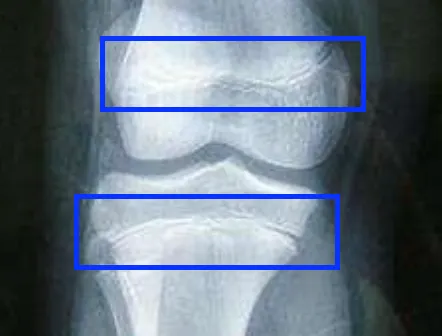

生長板並不是一塊板子,而是形狀類似板子、存在於長骨末端的組織,是一塊由軟骨構成的『區域』,能夠幫助骨骼變長、延伸。在X光影像上「看到」的生長板是一條黑色的縫隙。

(未密合的生長板)